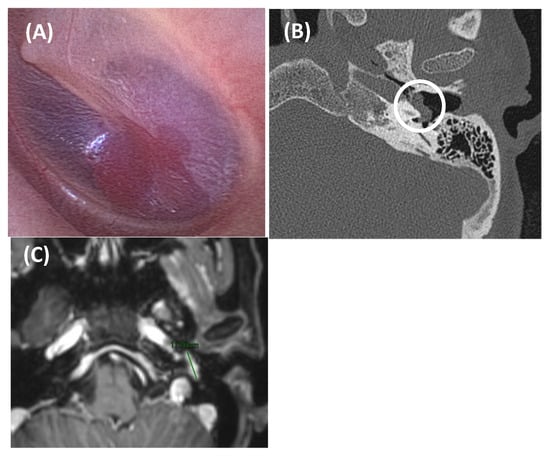

Figure 3. Aberrant intratympanic course of the right internal carotid artery, which is in contact with the cochlea (yellow arrow: aberrant ICA; blue arrow: cochlea). A 33-year-old man with right-sided PT of several years’ duration. Otoscopy revealed a pulsatile tumor in the right ear. CT imaging (A), axial plane bone window; (B), axial plane, contrast enhanced with soft tissue window; and (C), MPR coronal plane reconstruction) demonstrated a space-occupying lesion with a tubular appearance in the right mesotympanum, adjacent to the cochlear promontory, along with an enlarged inferior tympanic canaliculus and absence of the carotidotympanic bone septum.

Another potential cause of PT involves anatomical variants affecting the arteries at the base of the skull, with the aberrant ICA being the most common (Figure 3). In these patients, the ICA may take a different pathway, deviating from its normal anteromedial course through the petrous carotid canal to extend laterally into the middle ear. This variant is thought to arise when the cervical portion of the ICA either fails to develop properly or regresses. Consequently, the inferior tympanic and caroticotympanic arteries (two embryonic vessels) enlarge to compensate for the missing segment of the ICA [1,10]. The inferior tympanic artery typically extends laterally through the temporal bone into the middle ear, and in the case of an aberrant ICA, it follows a very similar course [1,37,38]. On otoscopy, a pulsatile vascular structure might sometimes be visible behind the tympanic membrane in cases of an aberrant ICA, which can occasionally be dehiscent. The carotid pulse is directly transmitted to the membranous labyrinth, leading to the perception of PT. It is crucial to conduct appropriate imaging studies (CT and MRA) to identify this variant, as it can sometimes be mistaken for a tympanic paraganglioma, a misdiagnosis with potentially catastrophic consequences during surgical intervention. If the ICA dehiscence is misdiagnosed and approached surgically, injury to the artery may occur and potentially result in massive hemorrhage, stroke, or even fatality [22].

We refer to dehiscent ICA when there is thinning or absence of the normal bony covering of the ICA, typically near the basal turn of the cochlea. This condition can be confirmed through imaging studies such as CT scans. The lack of bony separation allows for the direct transmission of the arterial pulse from the ICA to the membranous labyrinth, potentially causing PT and also appearing as a vascular mass behind the tympanic membrane. ICA dehiscence can occur with or without the presence of an aberrant ICA [1,10].